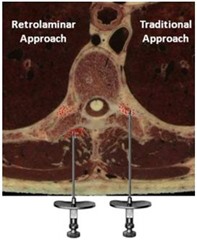

下図はCan J Anesth 2013; 60: 888-95からとってきました。

傍脊椎ブロック,retrolaminar block,paravertebral block,椎弓板

椎弓板のところで局所麻酔薬を注入すれば良いということなのです。

椎弓板のところで注入された薬剤は、傍脊椎腔まで広がっていき作用するというのです。

つまり、そこら辺というのはかなり疎な構造であり、穴ぼこがポコポコあいていて

傍脊椎腔まで薬剤が浸潤するということです。